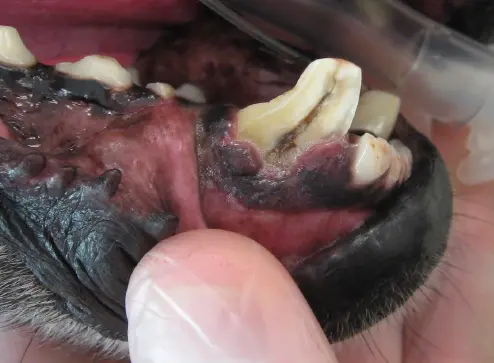

A fractured lower canine tooth in a dog. The dark, central part is exposed pulp canal

Fractured teeth hurt and become infected . The tooth is comprised of three main layers: the outer enamel, the middle dentin, and the inner pulp. The pulp contains living tissue made up of arteries, veins, lymphatics, connective tissues, and nerves. This is where the sensory pain receptors are located. The pulp, when exposed, may appear pink or black (as seen above).